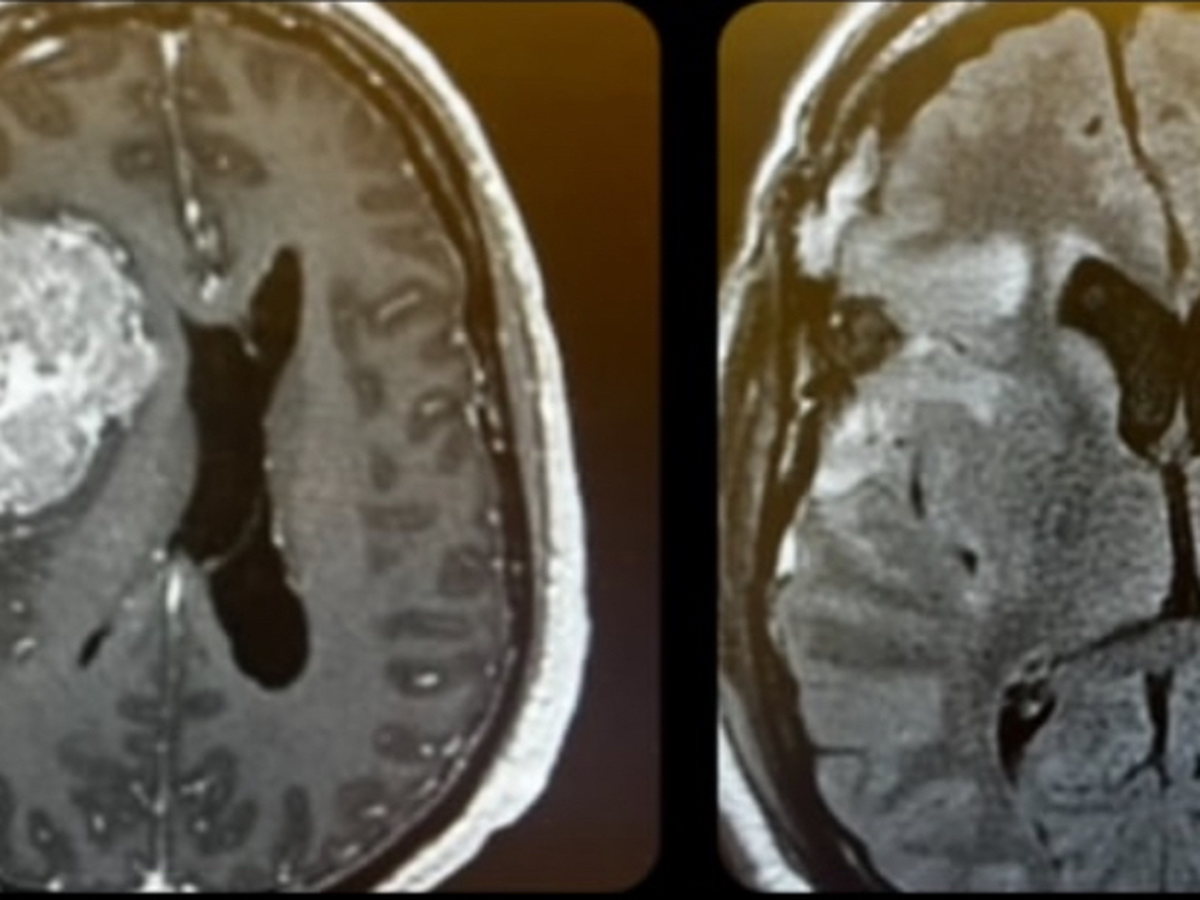

The first surgery, on December 19, removed the tumor that you'll see in the pic. It took up about a fourth of my brain and pushed it over, causing a CSF leak, which was repaired on January 30 during the second surgery. I am very lucky and grateful to be alive and to be able to function on my own, under the circumstances.